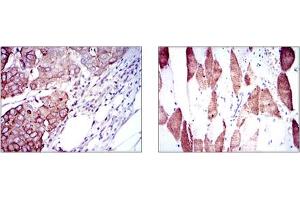

RPS6KB1 Reaktivität: Human, Maus, Ratte WB, IHC, ELISA, IF Wirt: Kaninchen Polyclonal unconjugated

RPS6KB1 Reaktivität: Human WB, IHC (p) Wirt: Kaninchen Polyclonal RB11404 unconjugated

RPS6KB1 Reaktivität: Human, Maus, Ratte WB, IF, IHC (p) Wirt: Kaninchen Polyclonal unconjugated

RPS6KB1 Reaktivität: Human WB, IHC (p) Wirt: Kaninchen Polyclonal unconjugated